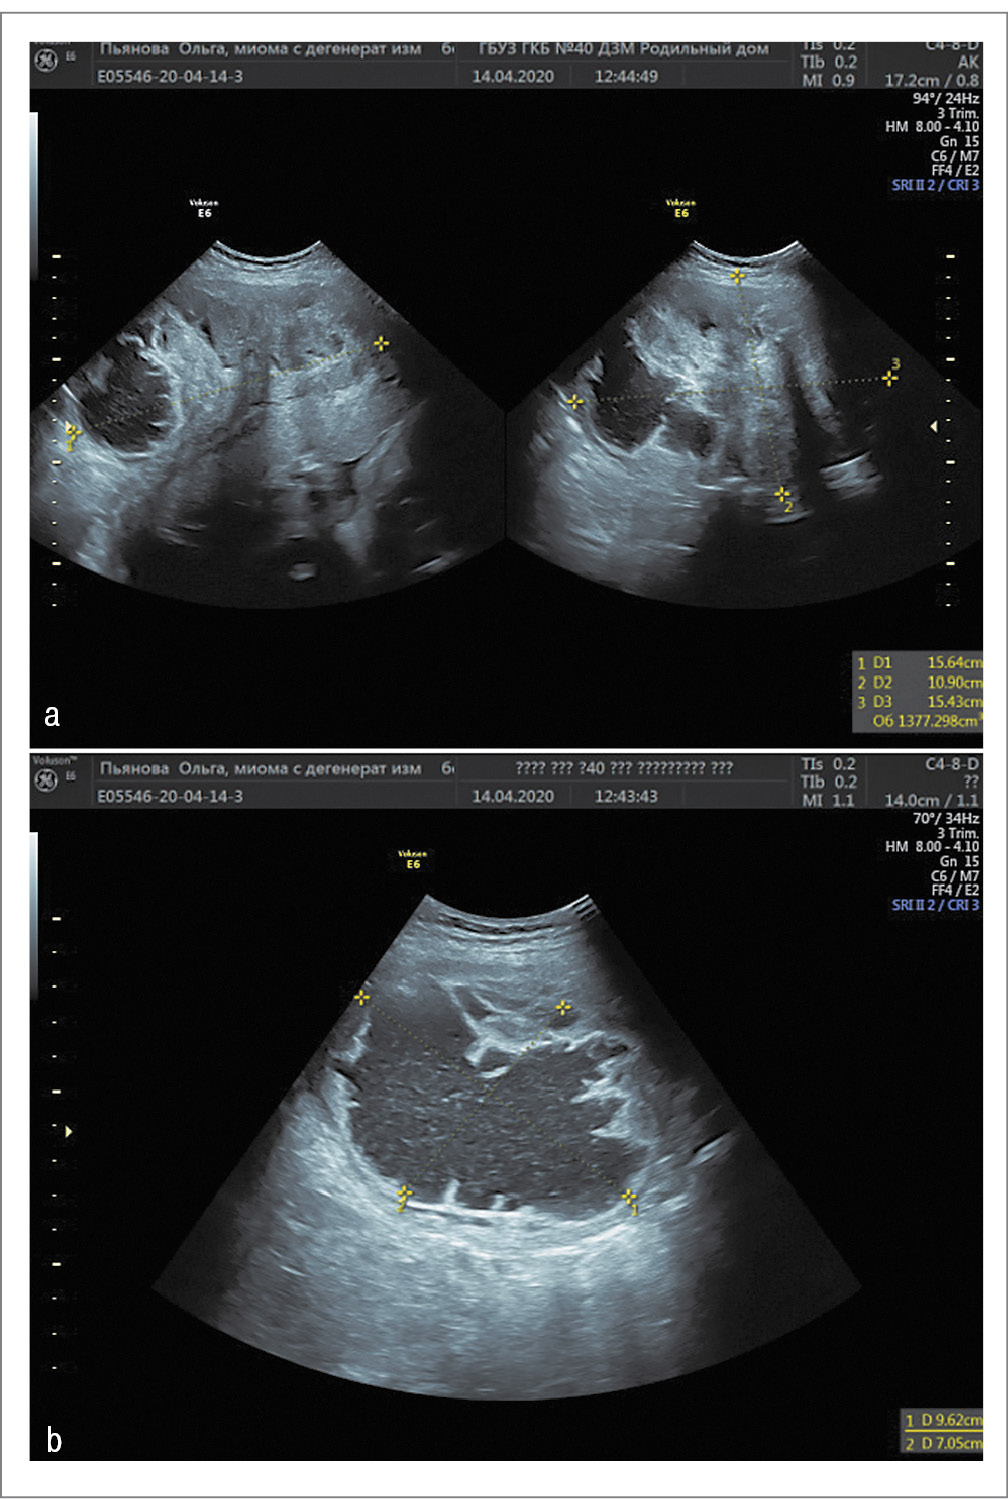

В 24 нед беременности при УЗИ субсерозный миоматозный узел был размером 170×113×116 мм (объем – 1170 см3), неоднородной структуры с участками повышенной, пониженной эхогенности, с кистозными полостями (наибольшая – размером 74×70 мм) и интенсивным интранодулярным высокоскоростным кровотоком (36 см/с, индекс резистентности IR=0,57); рис. 1.

Рис. 1. Миома матки в 24 нед беременности: а – миоматозный узел; b – ЦДК в узле; c – кистозные полости в узле. / Fig. 1. Uterine fibroids at 24 weeks of pregnancy: a – myomatous node; b – color flow mapping in the node; c – cystic cavities in the node CFM.